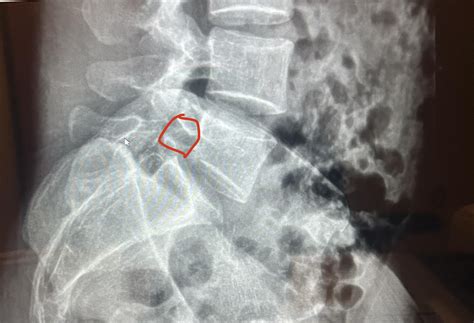

Spondylolisthesis is a condition where one vertebra slips forward over the vertebra below it. This condition can cause significant discomfort and mobility issues, particularly when it progresses to more severe grades. One of the milder forms of this condition is Spondylolisthesis Grade 1, which involves a slip of less than 25% of the vertebral body. Understanding this condition, its causes, symptoms, diagnosis, and treatment options is crucial for managing it effectively.

Spondylolisthesis Grade 1 is characterized by a slight forward slip of one vertebra over the one below it, typically less than 25% of the vertebral body. This condition can occur in various parts of the spine but is most commonly found in the lumbar region, particularly at the L5-S1 level. The slip can be caused by several factors, including degenerative changes, trauma, or congenital abnormalities.

• Imaging Tests: X-rays, CT scans, and MRI scans are commonly used to visualize the spine and determine the degree of slippage.

Imaging tests are particularly important for confirming the diagnosis and assessing the severity of the condition. X-rays can show the alignment of the vertebrae, while CT scans and MRI scans provide detailed images of the soft tissues and nerves.